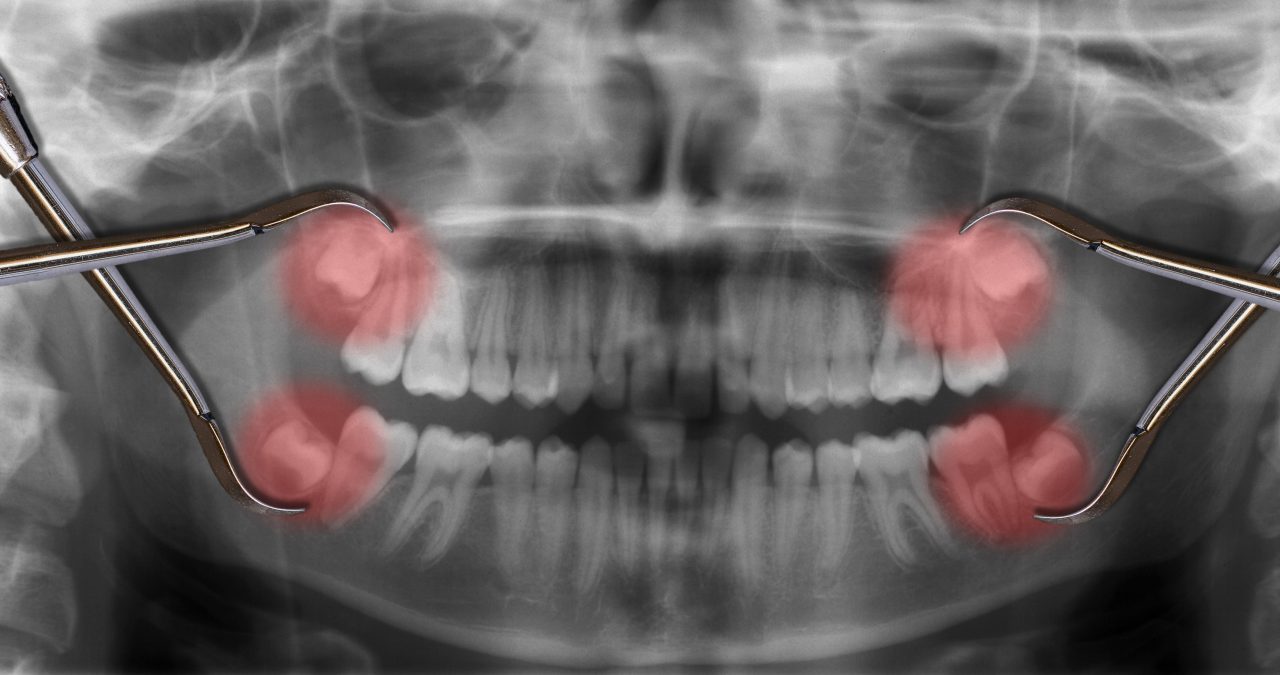

Neste caso, provavelmente, ele terá auxílio de exames como os de raio-X para conhecer e confirmar a posição exata do dente antes da cirurgia.

Como é a extração do dente siso?

Normalmente, a extração do siso é feita como a de outros dentes: anestesia local e uma breve cirurgia de aproximadamente 30 minutos. Após a remoção, o dentista faz a sutura.

No entanto, essa complexidade é medida pelo posicionamento do dente, o que determina se o procedimento será mais ou menos trabalhoso.